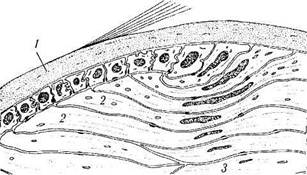

Определяются следующие структурные элементы хрусталика (рис. 3.4.4—3.4.6):

Рис. 3.4.4. Схема микроскопического строения хрусталика:

/ — капсула хрусталика; 2 — эпителий хрусталика центральных участков; 3 — эпителий хрусталика переходной зоны; 4 — эпителий хрусталика экваториальной области; 5 — эмбриональное ядро; 6 — фетальное ядро; 7 — ядро взрослого; 8 — кора

Рис. 3.4.5. Особенности строения экваториальной области хрусталика (по Hogan et al., 1971):

I — капсула хрусталика; 2 — экваториальные эпителиальные клетки; 3 — хрусталиковые волокна. По мере пролиферации эпителиальных клеток, расположенных в области экватора хрусталика, они смещаются к центру, превращаясь в хрусталиковые волокна